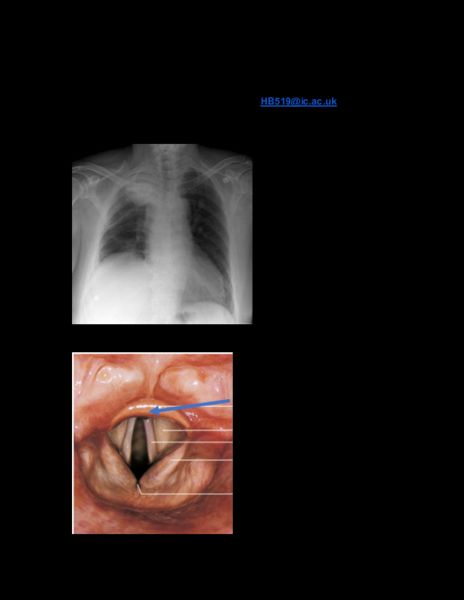

ICSM Surgical Society- Junior Anatomy Series - Thorax and Heart Mock Author: Harroop Singh Bola (HB519@ic.ac.uk) 1). What can cause this pathological condition? Answer: Right phrenic nerve palsy In phrenic nerve palsy, the hemidiaphragm supplied by the affected portion is elevated. 2). Identify the labelled structure Answer: Epiglottis3). Describe the function of the labelled structure Answer: Humidification and warming of inspired air. 4). Answer: Chordae tendineae The labelled structure is the tricuspid valve, contraction of the papillary muscles causes the chordae tendineae to close the valve, and prevent from being inverted into the right atrium. Which structure prevents the labelled valve from being inverted into the right atrium?5). Answer: Internal intercostal muscle Deep to the external intercostal muscles, the direction of the fibres latero-inferiorly. What muscle is indicated by the arrow? 6). Answer: C5 Structure 10 is the oesophagus Structure 10 begins at which vertebral level? 7). What surface landmark is associated with Answer: Sternal Angle (Angle of Louis) structure 3? The arch of the aorta is found at the T4 vertebral level.8). Stiffening of this structure can cause what Answer: Ejection systolic murmur pathological heart sound? Labelled structure is an Aortic valve. Remember that the pulmonary valve lies on top of the aortic valve. Aortic stenosis causes ejection systolic murmur and can be auscultated at the carotid artery. This sound happens between the normal S1 (lub) and S2 (dub) sounds. 9). Label the following structure Answer: Oblique Fissure Separates the superior from the inferior and middle right lung lobes.10). Which specific cardiac chamber does the Answer: Right Ventricle labelled vessel arise from? The mediastinal surface of the right lung is illustrated, as determined by the absence of a cardiac impression, in addition to the presence of three lung lobes - Upper, middle and lower. Pulmonary arteries transport blood out of the right ventricle into pulmonary circulation for oxygenation. 11). Which structure is more prone to inhalation of Answer: Right Main Bronchus a foreign object? The right main bronchus is steeper and wider comparatively to the left main bronchus, therefore is more susceptible to the aspiration of foreign objects. 12). Label the following the structure Answer: Carina A cartilage situated at the point where the trachea divides into the two bronchi. 13). Which structure resides most inferiorly to the Answer: Intercostal Nerve label? Labelled is the costal groove, to which the neurovascular bundle resides (VAN), from superior to inferior: Vein, Artery, Nerve.14). At which vertebral level does the labelled Answer: T8 structure penetrate the diaphragm at? Superior vena cava is labelled. Vena Cava = 8 letters, therefore T8. 15). What is the specific labelled vessel? Answer: Left Common Carotid Artery16). What is the anatomical surface landmark of the Answer: Midclavicular line, left 5th intercostal space. labelled structure? Labelled: Apex of the heart17). Which vessel supplies this structure? Answer: Right coronary artery Labelled: Right atrium 18). Where does the labelled vessel originate from? Answer: Left Aortic Sinus of the ascending aorta Labelled: Left coronary artery19). Which specific cardiac structure does the Answer: Sinoatrial node labelled artery supply? Labelled: Sino-atrial nodal branch of the right coronary artery. 20). What is the origin of the labelled artery? Answer: Right Coronary Artery Labelled: Posterior interventricular artery21). What is the labelled structure? Answer: Coronary Sinus 22). Where do the labelled vessels drain into? Answer: Coronary Sinus Labelled: Middle cardiac veins23). Inflammation of the following structure Answer: Myocarditis manifests as what pathology? Labelled: Myocardium 24). What is the precursor of the labelled structure? Answer: Foramen Ovale Labelled: Fossa Ovalis25). What is the following labelled structure? Answer: Pectinate muscle 26). Which heart sound is auscultated upon the Answer: S2 closure of the labelled valve? Labelled: Pulmonary valve27). What is the specific structure labelled below? Answer: Posterior aortic sinus Non-coronary, there is no coronary artery arising from this sinus. 28). What is the specific structure labelled? Answer: Thoracic ganglia29). Label the following structure Answer: Left Oblique Fissure Coronal CT, IV contrast using lung windows 30). Label the following structure Answer: Ascending Aorta31). Label the following structure Answer: Sternal Angle 32). What lung pathology is demonstrated by the Answer: Right-sided tension pneumothorax chest radiograph?33). Name the following structure Answer: Jugular (Suprasternal) Notch 34). Which rib is shown below? Answer: First rib Presence of scalene tubercle, and subclavian grooves.35). Which category of ribs is shown below? Answer: False ribs Unification of cartilage, and thus do not have a direct articulation with the sternum. 36). Which pericardial layer is shown below? Answer: Fibrous pericardium37). What is the foetal derivation of the following Answer: Ductus arteriosus structure? Labelled: Ligamentum arteriosum 38). The two vessels unite to form what vessel? Answer: Left Brachiocephalic vein Labelled: Subclavian and internal jugular vein 39). Which nerve is labelled below? Answer: Left Vagus Nerve 40). Label the following muscle Answer: External intercostal muscle41). What is the primary function of the labelled Answer: Forced Expiration muscle? Labelled: Internal Intercostal Muscles 42). What is the labelled structure? Answer: Internal Thoracic Artery 43). What is the labelled structure? Answer: Serous pericardium44). What is the specific part of the lung labelled? Answer: Left Apex 45). Name the specific structure of the lung Answer: Lingula of left lung